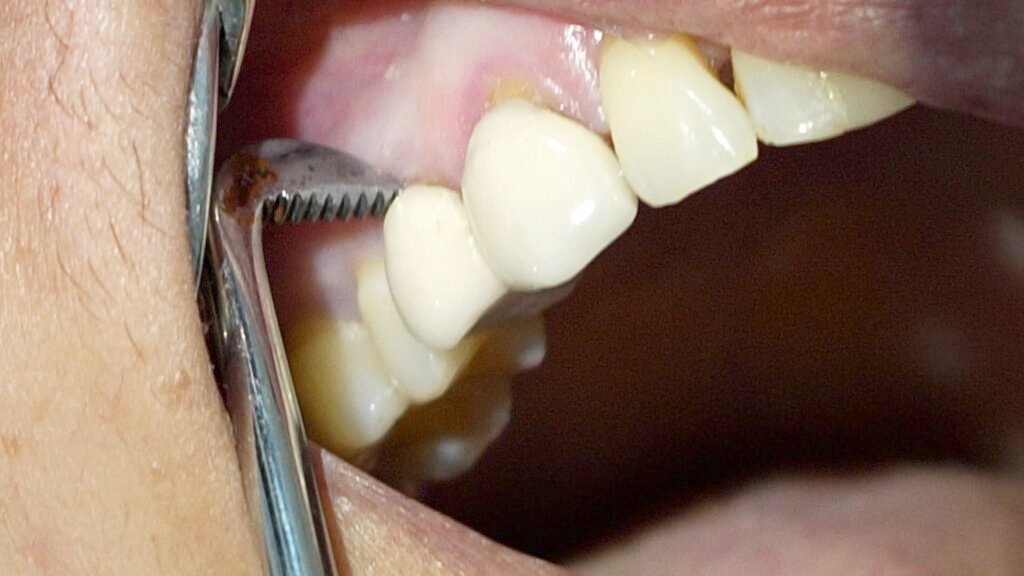

I explained the situation to the patient, noting that the tooth had been treated improperly and both the tooth and broken file would need to be removed. After removing the porcelain crown, I found that the restoration underneath was temporary and that dental caries were not properly cleaned out—an important first step before any root canal treatment